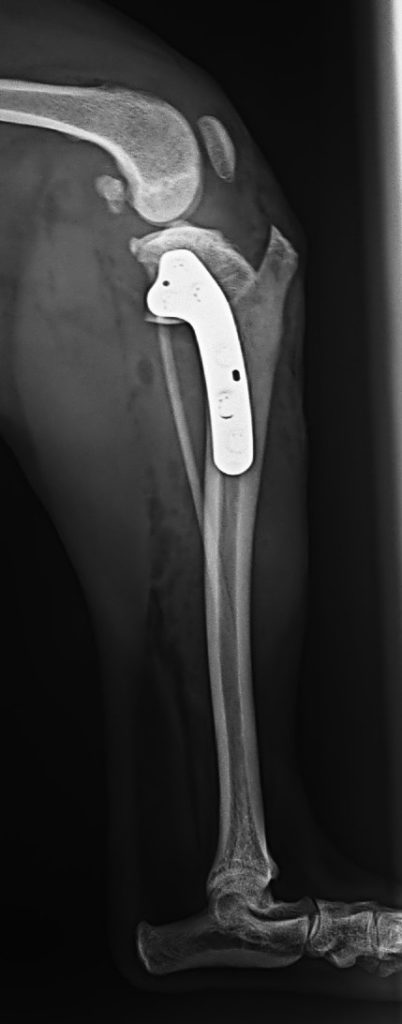

- 前十字靱帯断裂(TPLO:脛骨高平部骨切り術)

・TPLO(前十字靭帯断裂に対する脛骨水平化骨切り術) 45万円前後